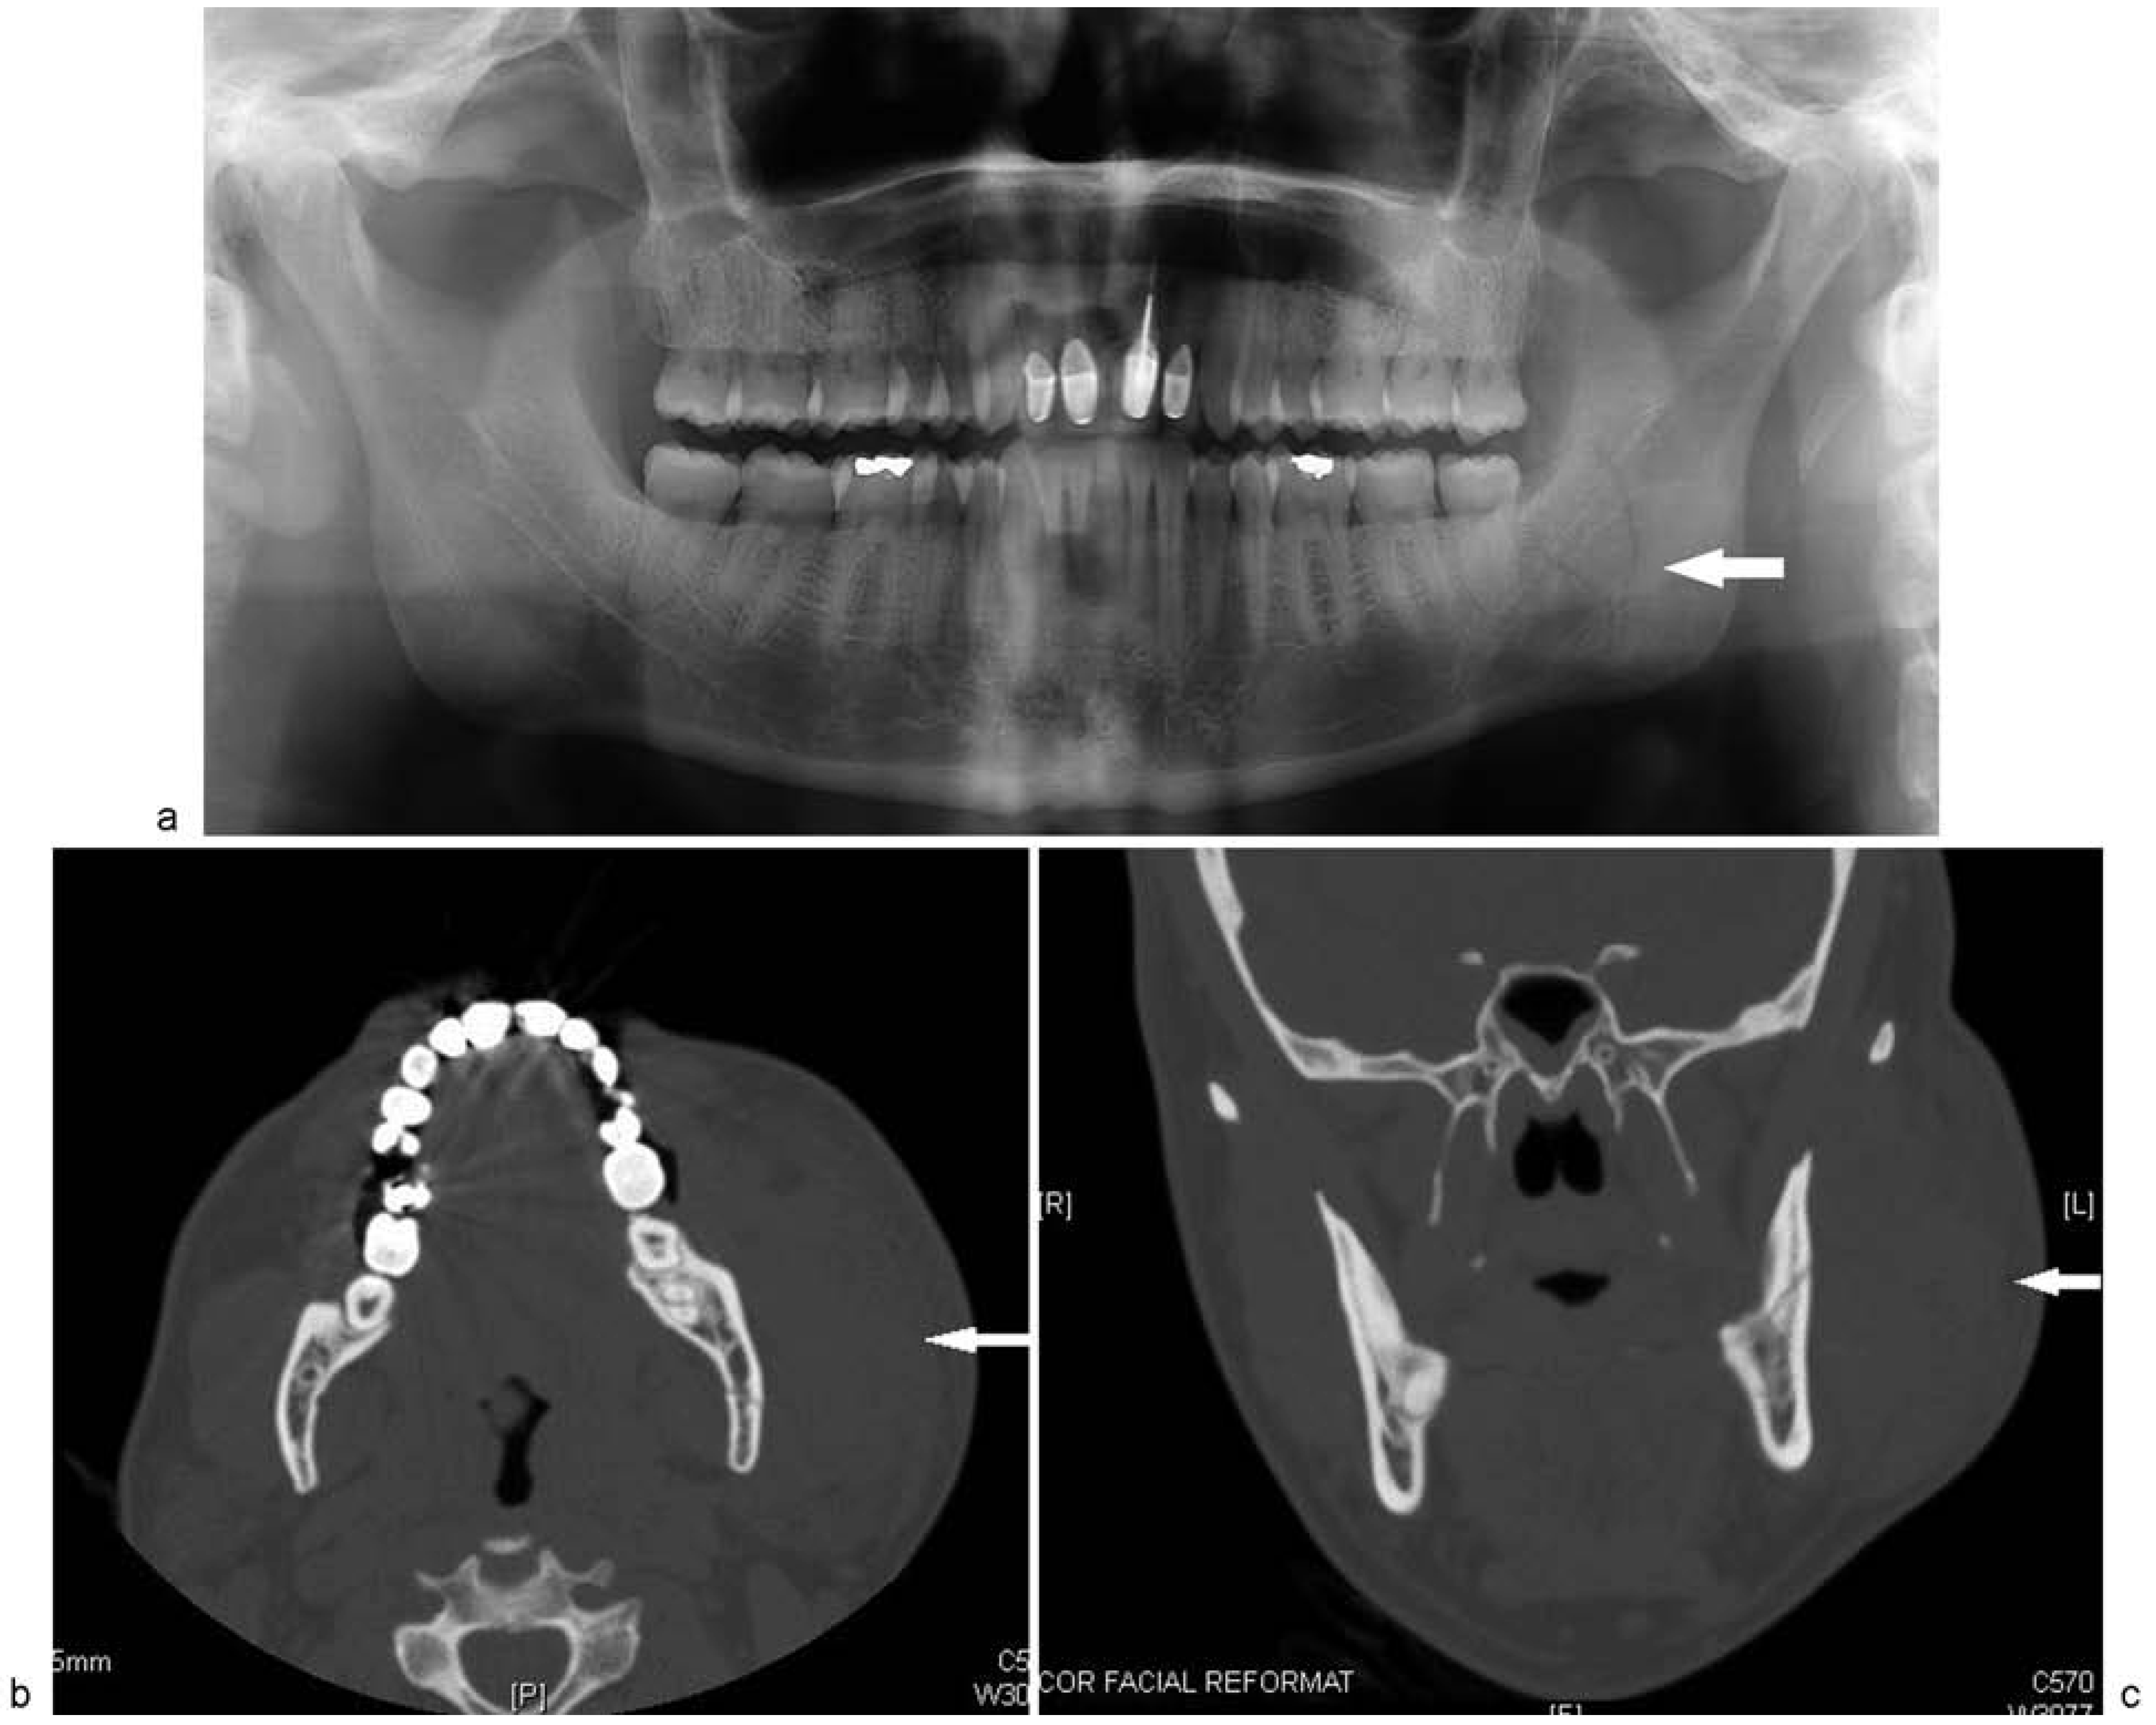

Computed tomography (CT) of the face was positive for a minimally displaced fracture of the left mandibular angle that was continuous with the periodontal ligament space of an erupted nonfunctional lower left third molar (Figure 1a–d). Inaddition to left mandibular angle fracture, the radiologist noted left-sided soft-tissue fullness that was thought to represent a possible hematoma that was 3.4 × 5.5 cm (Figure 2).

In the case presented, disruption of the glandular substance was evident on the initial CT, but was initially interpreted as representing a possible hematoma. This case illustrates the need for careful assessment of soft tissues on initial CT scans taken for maxillofacial trauma. A high index of suspicion for soft tissue injury should be maintained while reviewing scans to ensure diagnoses are not missed.

Figure 2. Preoperative CT scan showing left-sided perimandibular fluid collection. This was initially read as a possible hematoma by the radiologist. Further inspection shows an intracapsular parotid fluid collection consistent with a sialocele.